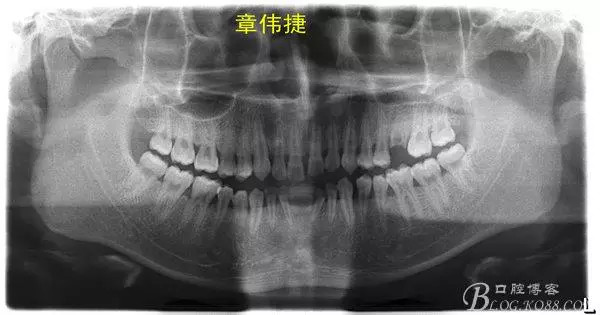

患者成年男性因下合牙間隙大,曾經(jīng)咨詢過多家醫(yī)院,建議修復(fù),但患者拒絕,來(lái)萬(wàn)眾口腔醫(yī)院正畸科就診。

術(shù)前資料: